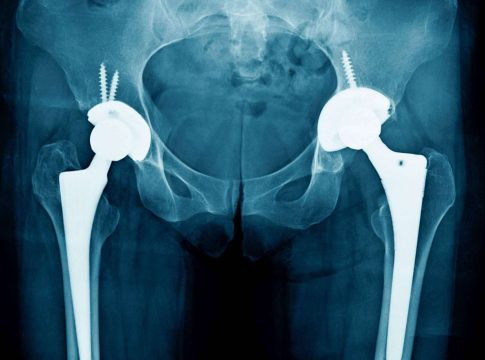

Sobre la artropatía degenerativa explican que sus causas no están del todo claras. Pueden ser generadas por lesiones, accidentes o sobrecargas persistentes que van acumulando un deterioro progresivo en las articulaciones. También se relaciona con posturas incorrectas que algunas personas tienen de nacimiento y con factores hereditarios relacionados con la genética familiar.

La artropatía degenerativa es una patología crónica cuyos síntomas se manifiestan con rigidez y sensación de tensión en la articulación afectada. También son frecuentes los crujidos o chasquidos al moverse y la sensibilidad aumentada cuando el paciente se enfrenta a climas húmedos. Cómo es lógico, en muchos casos, el síntoma más incómodo suele ser el dolor.